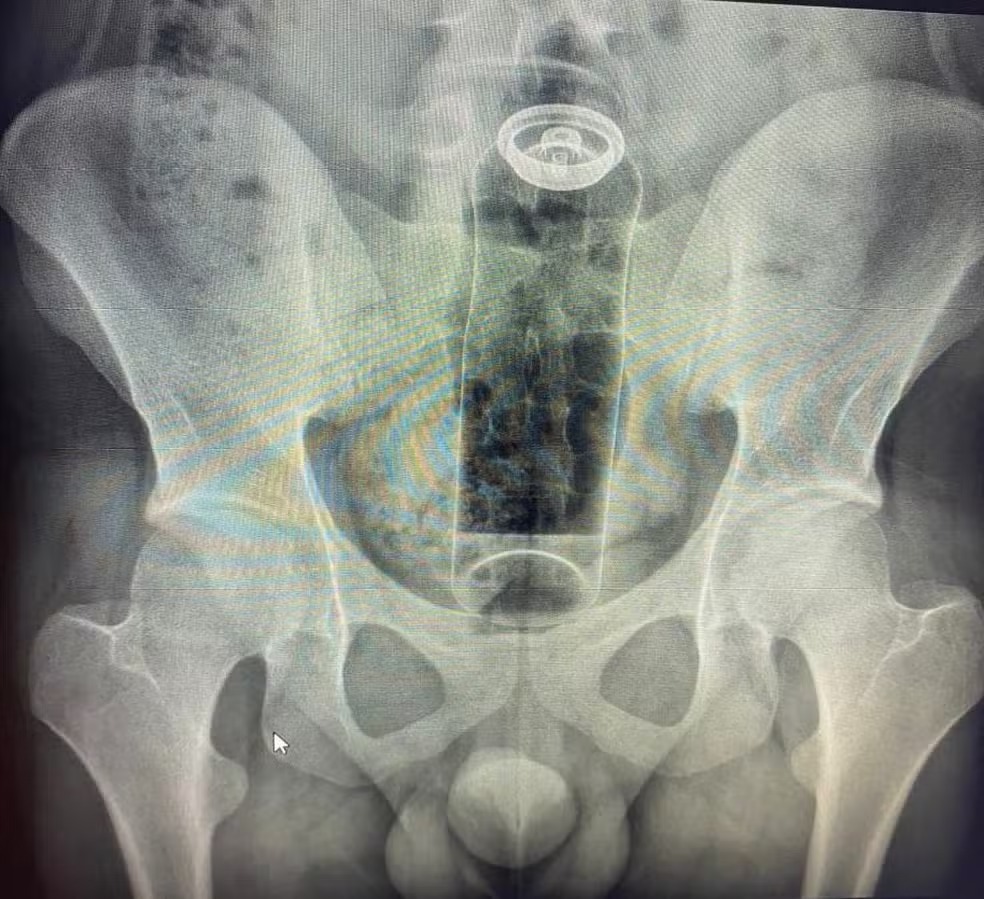

Seja por curiosidade, desejo de apimentar a relação ou pela descoberta da própria sexualidade, a prática do sexo anal é comum entre muitas pessoas. Especialistas alertam, no entanto, que a exploração da região exige cuidados, especialmente em relação aos objetos utilizados. O alerta ganhou repercussão após um médico relatar, nas redes sociais, o atendimento a um jovem que precisou ser internado para retirar um desodorante que ficou preso no reto.

De acordo com o cirurgião coloproctologista Daniel Brosco, o paciente, de 19 anos, contou que introduziu o objeto no ânus durante uma brincadeira sexual. A embalagem acabou sendo sugada pelo intestino e não pôde ser removida em casa, exigindo intervenção médica. Segundo o especialista, o problema não está na fantasia ou na prática sexual, mas no uso de objetos inadequados, que podem causar lesões graves, infecções e até levar à morte.

A região anal possui muitas terminações nervosas e pode ser estimulada com segurança. O sexo anal, por si só, não causa doenças como hemorroidas, conforme explicam os especialistas. No entanto, o intestino pode “puxar” objetos para dentro devido aos movimentos peristálticos contrações involuntárias responsáveis pelo funcionamento do órgão ou pelo efeito de vácuo no reto, fazendo com que fiquem presos rapidamente.

O médico afirma que esse tipo de ocorrência tem se tornado cada vez mais frequente. Nos últimos meses, ele já atendeu casos envolvendo objetos como batata, partes de cadeira, garrafa de vidro e até plug anal. A orientação é procurar atendimento hospitalar imediatamente e jamais tentar soluções caseiras, como o uso de laxantes, que podem agravar a situação.